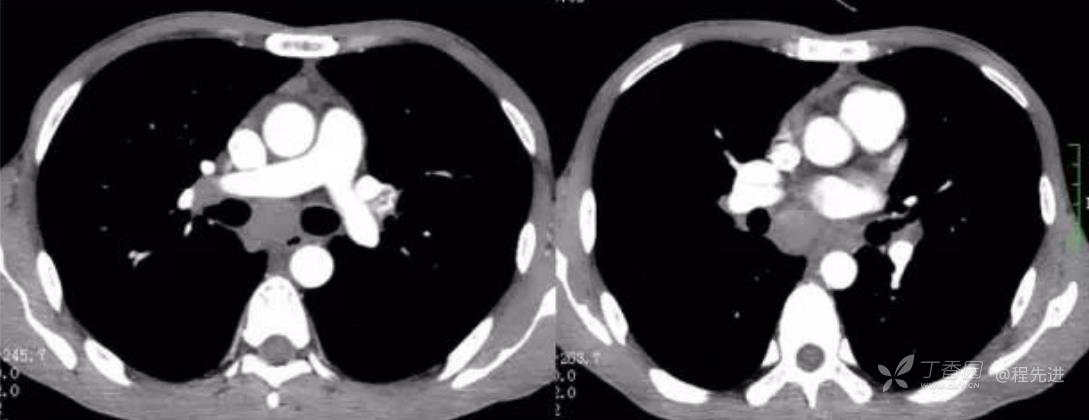

CT平扫肺窗

平扫纵隔窗